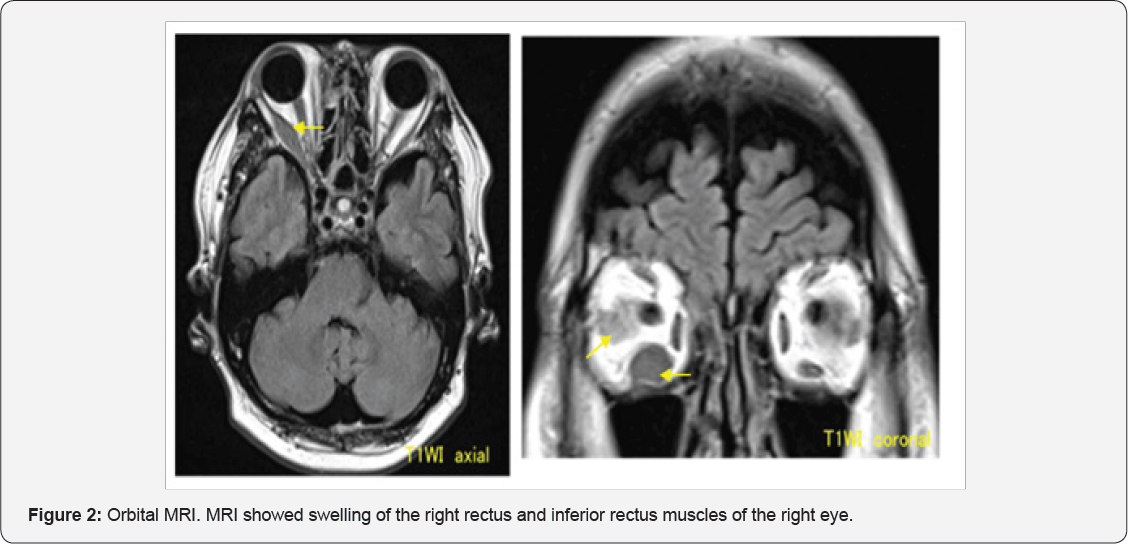

A 60-year-old man was examined because of blurred vision in the right eye. The right eye exhibited an ocular motility disorder in all directions. Three days later, he was referred to our department. His medical history included acute ATLL diagnosed 2 years earlier, with complete remission after chemotherapy. He also had a thyroid adenoma, which was diagnosed by biopsy. The findings at initial examination were as follows, corrected visual acuities20/20 OU, pupil diameters, 5 and 6mm in the dark and 3 and 3mm in room light, for the right and left eyes, respectively. The pupillary light reflex was rapid and complete, and the relative afferent pupillary defect (RAPD) was negative. Before the use of 1% apraclonidine eye drops, the pupil diameters of the right and left eyes were7 and 6mm, respectively. The right eye exhibited restricted abduction and depression as well as exophthalmos (Figure 1). Hertel exophthalmometer was 24mm OD, 19mm OS. The force deduction test was positive. No abnormalities were in the anterior ocular segment, optic media, or ocular fundus. His plane MRI showed swelling of the lateral rectus and inferior rectus muscles of the right eye (Figure 2). Orbital diseases in the right eye, such as thyroid eye disease, orbital myositis, and Horner syndrome were thought to be affecting the thyroid adenoma biopsy. One month later, the symptoms worsened. His corrected visual acuities 20/60 OD, 20/20 OS and right-eye RAPD was detected. In addition, chemosis, increased intraocular pressure, and optic disc swelling were observed (Figure 3). Thus, the patient was emergently admitted to our hospital. Enhanced orbital MRI showed the right medial rectus, lateral rectus, and inferior rectus muscles were more swelling. These muscles compressed the optic nerve at the orbital apex. The muscles were hypo intense on T1-weighted images and hyper intense on T2-weighted images, and showed a uniform enhancement effect. Diffusion-weighted images (DWI) showed hyper intense signals, and the apparent diffusion coefficient value was markedly low at 0.5. (Figure 4), suggestive of malignant lymphoma. We did biopsy of the inferior rectus muscle (Figure 5). Histpathologically, there was diffuse proliferation of lymphocytes containing small to large nuclei. Immunostaining tested positive for CD3 and CD4, and negative for CD8 and CD79a (Figure 6). Consequently, he diagnosed with ATLL cellular infiltration and recurrence of ATLL.